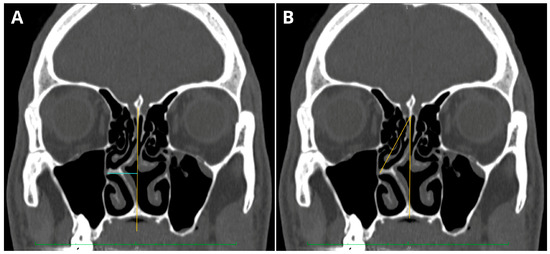

2.3. NSD Analysis

3.3. NSD Analysis